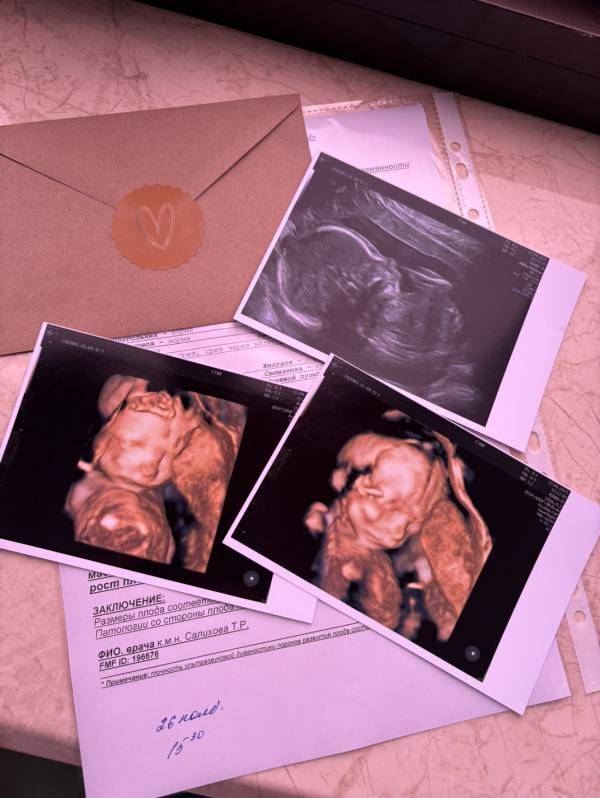

Вчера был долгожданный день, второй скрининг у любимой Салиховой Т.❤️ И мы наконец-то узнали, кто у нас там прячется 🥹

С лица на девочку похожа 😁и прячутся вроде обычно девочки